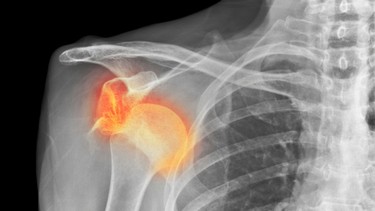

Trật khớp vai tái hồi là tình trạng khớp vai bị trật lặp đi lặp lại sau chấn thương ban đầu, thường gặp ở người trẻ và vận động viên. Nếu không can thiệp đúng cách, tình trạng này có thể gây suy giảm chức năng vai và ảnh hưởng lâu dài đến chất lượng cuộc sống.

Trật khớp vai tái hồi là tình trạng đầu xương cánh tay (chỏm xương cánh tay) liên tục trượt ra khỏi ổ chảo của xương vai do cấu trúc giữ khớp bị tổn thương sau lần trật khớp ban đầu. Đây là một trong những biến chứng phổ biến nhất sau trật khớp vai cấp tính, đặc biệt ở người trẻ, nam giới và những người thường xuyên tham gia các hoạt động thể thao hoặc lao động gắng sức.

Trong lần trật khớp đầu tiên, bao khớp, dây chằng và sụn viền quanh ổ chảo thường bị rách hoặc giãn. Sự tổn thương này khiến khớp vai trở nên lỏng lẻo và dễ bị trật lại, thậm chí chỉ với các động tác thông thường như giơ tay lên cao, xoay vai mạnh hoặc bị va chạm nhẹ. Mỗi lần trật khớp tiếp theo không những làm tăng nguy cơ tổn thương thêm các cấu trúc quanh khớp mà còn gây giảm chức năng vận động và đau kéo dài.